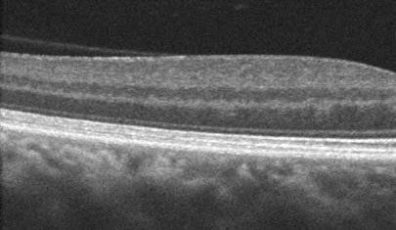

The retina lines the inside of the eye like wallpaper. It has multiple layers that are normally stuck together. Degenerative retinoschisis is an age-related disorder where these layers split.

Virtually all patients with degenerative retinoschisis are completely asymptomatic. The retinal splitting, which may be in one or both eyes, is detected by your eye doctor during a dilated retinal examination as a smooth solid retinal elevation.